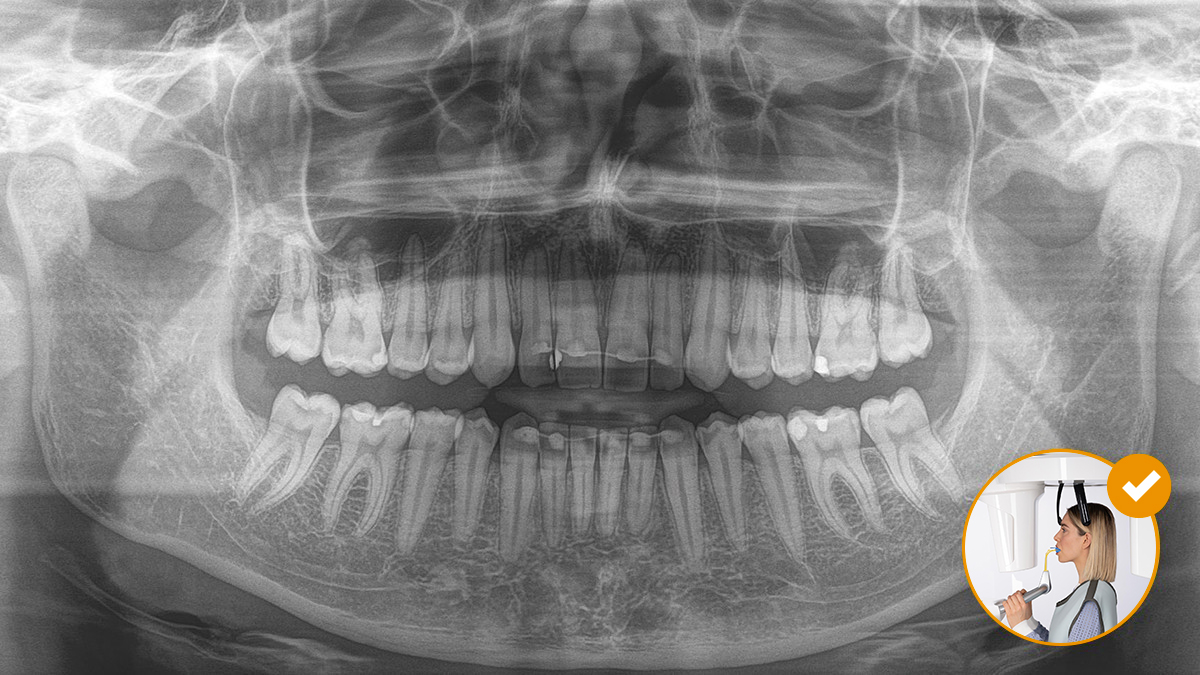

O posicionamento correto do paciente leva à alta qualidade da imagem para apoiar um diagnóstico preciso e facilita e melhora a experiência do paciente.

Este é o nosso conceito de 10 pontos para o fácil posicionamento do paciente e imagiologia por X. Consiste principalmente em dois pontos: alta qualidade de imagem e conforto para o paciente e para o assistente.

O resultado: digitalizações precisas graças ao bloco de mordida oclusal